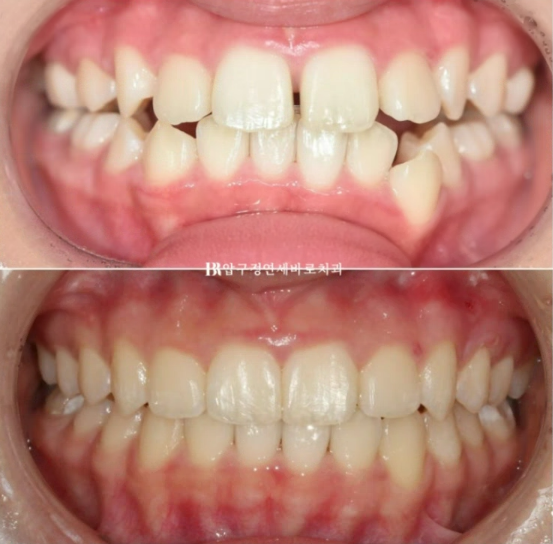

약 7개월에 걸쳐 첫번째 세트를 모두 낀 후의 모습입니다.

24.03

그리고 추가장치를 4달간 더 낀 후의 모습입니다.

중심선은 잘 맞아졌습니다.

23.08~24.07

무엇보다 한쪽의 3급 어금니 교합관계는 1급이 되었습니다.

치료가 잘 끝났으니 1년간의 변화를 보겠습니다.